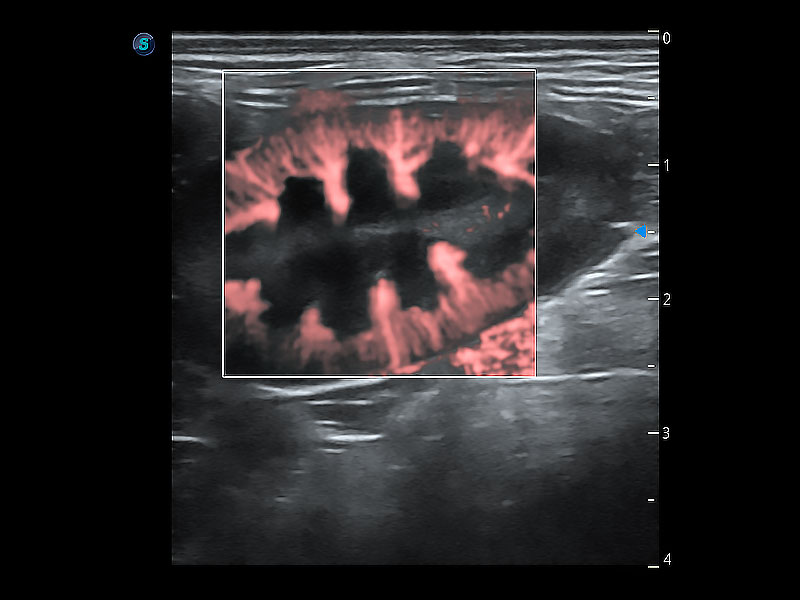

極大提升超低速微細血流的檢出能力,同時更精準地濾除軟組織和超聲信號,為獸用醫(yī)生提供以往無法通過常規(guī)血流獲得的疾病診斷信息。

在傳統(tǒng)二維血流成像的基礎(chǔ)上,呈現(xiàn)血流的立體感,具有動感的生命力之美。即便是微小的血管也能輕松應(yīng)對,提高了血流的視覺敏感性。